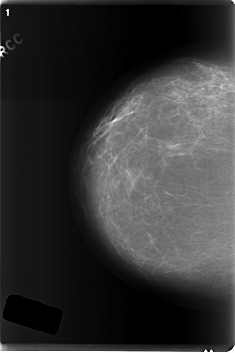

C_0219_1.LEFT_CC

RIGHT_CC LINES 5992 PIXELS_PER_LINE 3992 BITS_PER_PIXEL 12 RESOLUTION 50 NON_OVERLAY